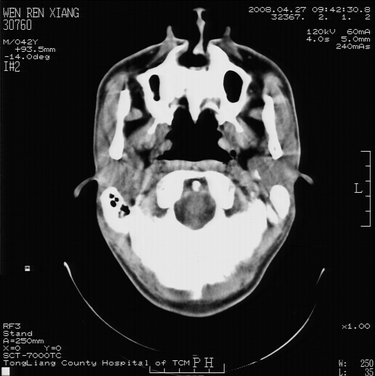

以下是引用随光逐影在2008-4-27 10:26:00的发言:[br]考虑为:上颌骨(中线区)含牙囊肿并向鼻腔穿破。

以下是引用前行在2008-4-27 11:30:00的发言:[br]含牙囊肿可能性大

以下是引用余辉在2008-4-27 16:43:00的发言:[br]考虑上颌骨正中囊肿,伴不全上颌骨正中裂,囊肿与鼻前庭有瘘道,所以表现为腔内炎性粘膜增厚而无囊液